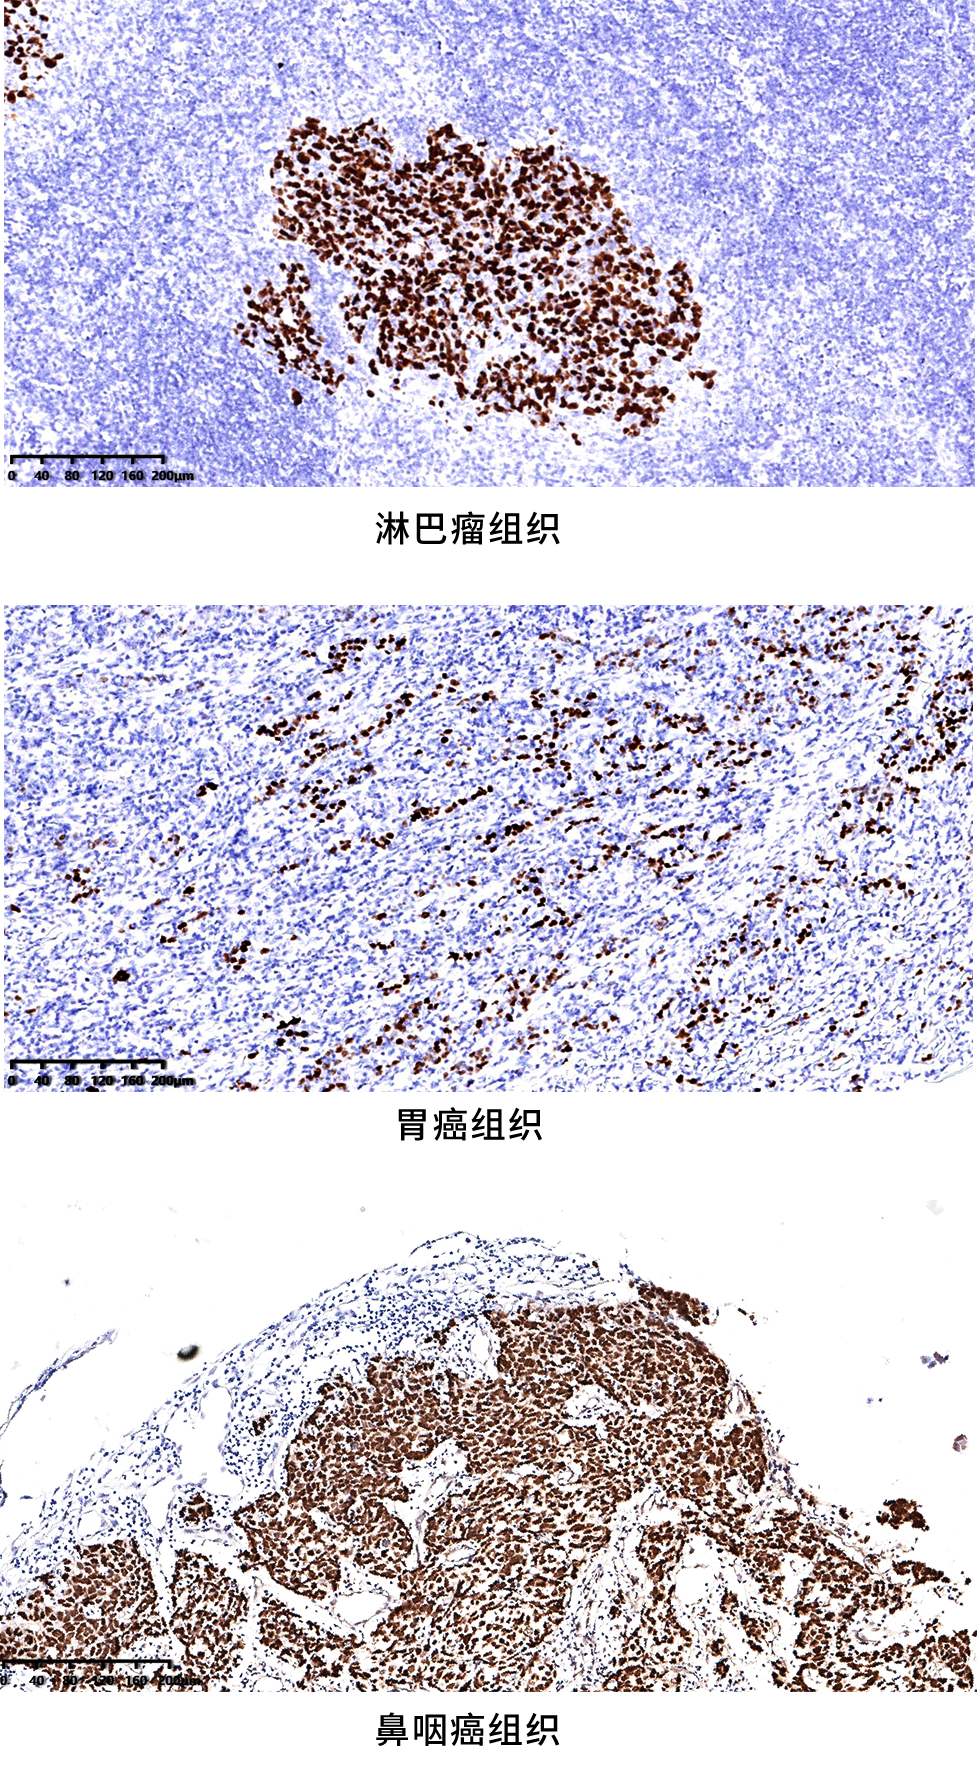

⑥ EBER染色效果圖

定位準(zhǔn)確,染色清晰無背景